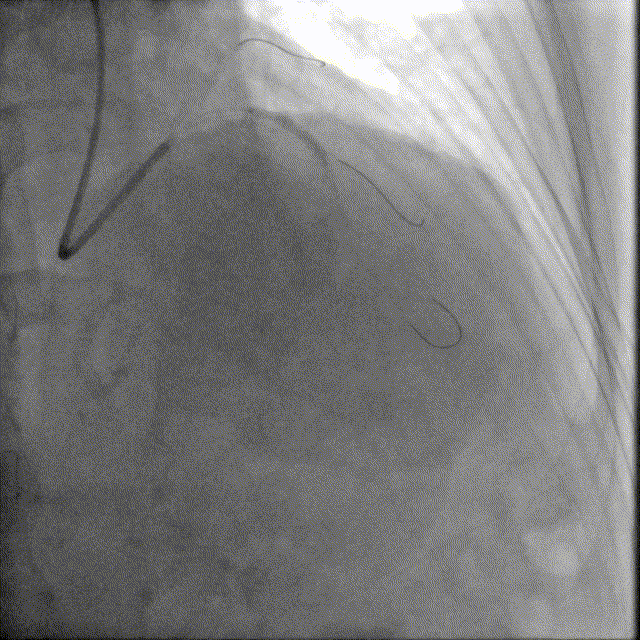

于前降支中段近段口串联2.5mm×18mm、3.0mm×18mm DES。

前降支开口精确定位植入3.5mm×18mm DES。

2.5mm-3.5mm后扩球囊后扩张。

最终结果满意,复查IVUS支架膨胀、贴壁良好!